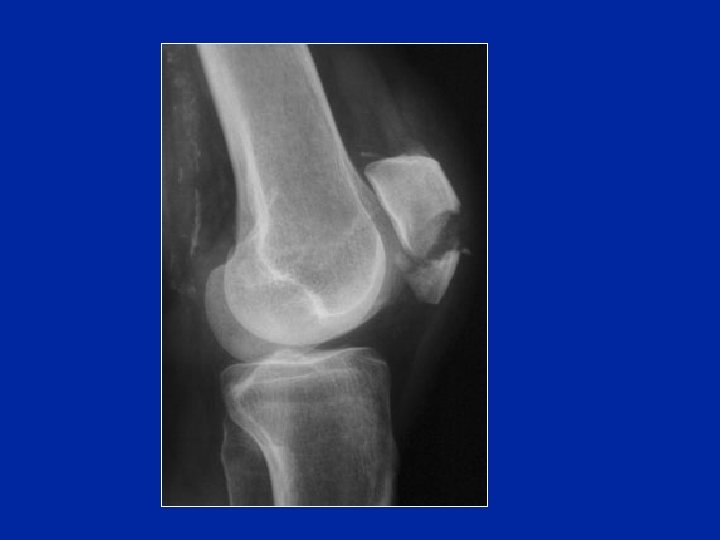

Le cadute sul ginocchio e le contusioni dirette in seguito ad incidenti della strada (trauma da cruscotto) sono le cause più frequenti

Fratture parcellari esterne

Distacco dell’inserzione dell’alare interno in seguito a lussazione di rotula

Fratture comminute Sono spesso esposte